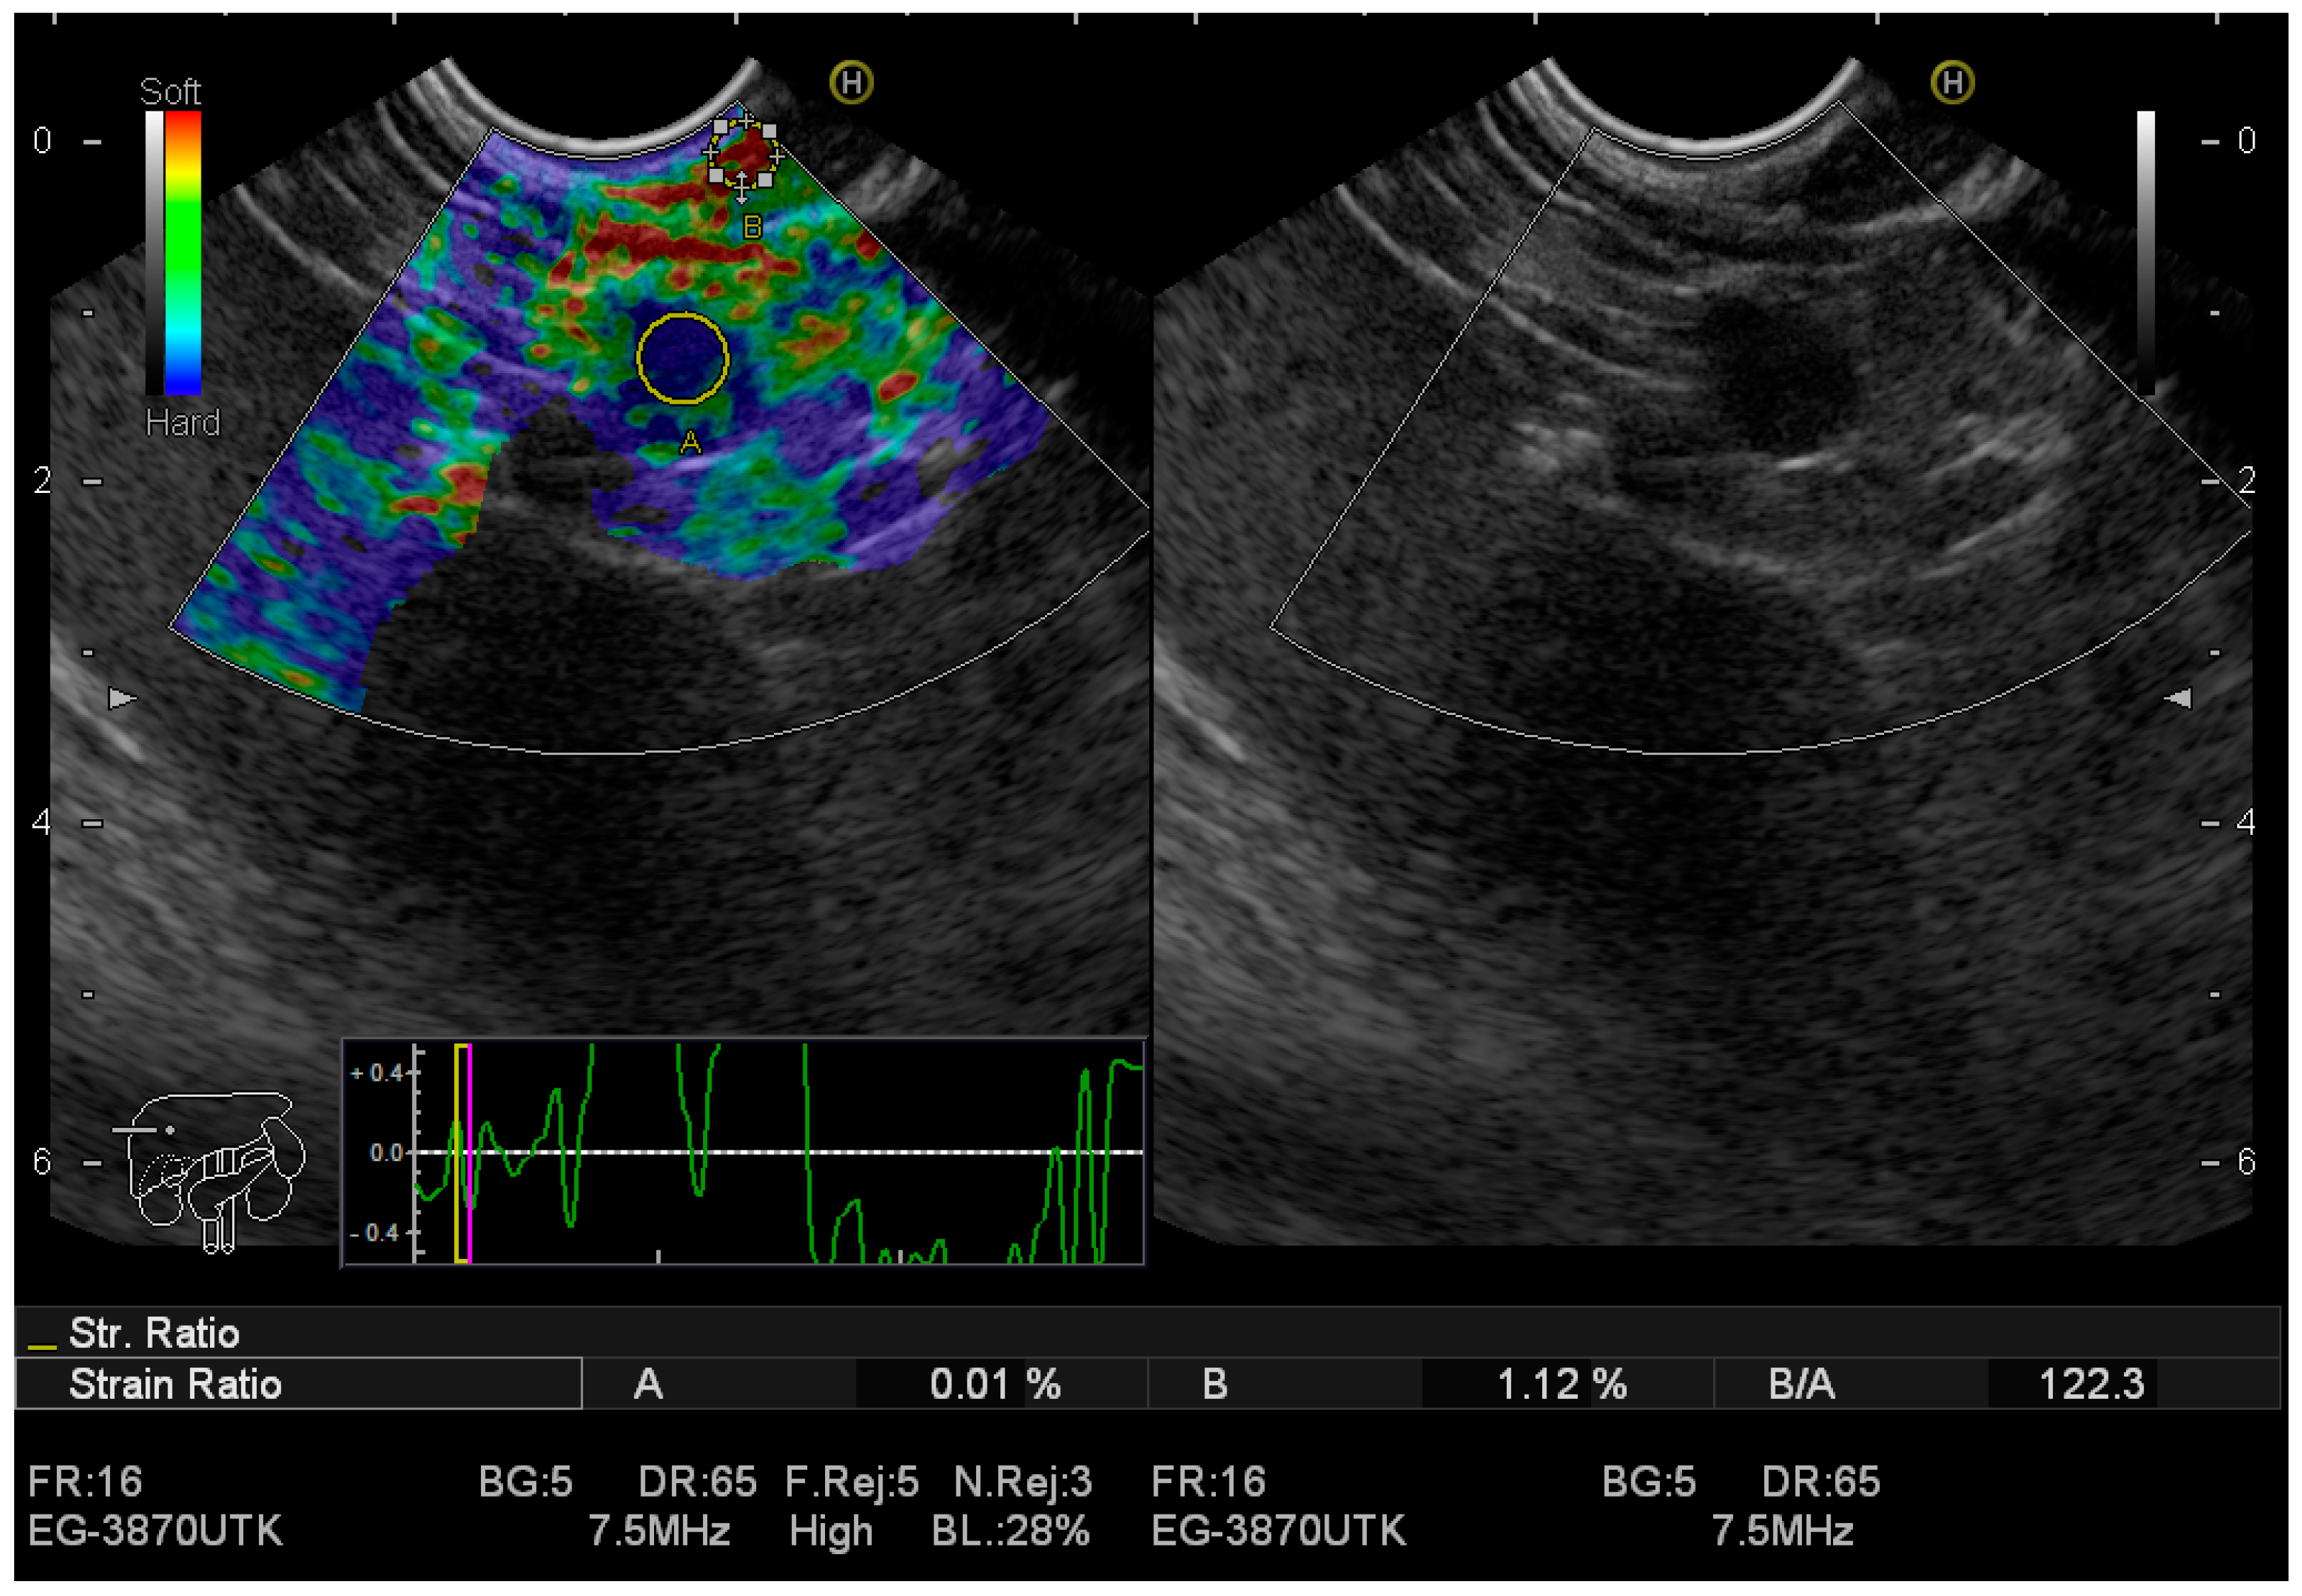

| Study | Cases | Sensitivity | Specificity | Diagnostic Odds Ratio | Comments |

|---|---|---|---|---|---|

| Zhang B et al. [62] | 1044 | 95% | 67% | 42.28% | EUS elastography |

| Lu Y et al. [63] | 1544 lesions | 97% | 67% | - | Qualitative methods |

| Lu Y et al. [63] | 1544 lesions | 97% | 67% | - | Strain histograms |

| Lu Y et al. [63] | 1544 lesions | 98% | 62% | - | Strain ratio |